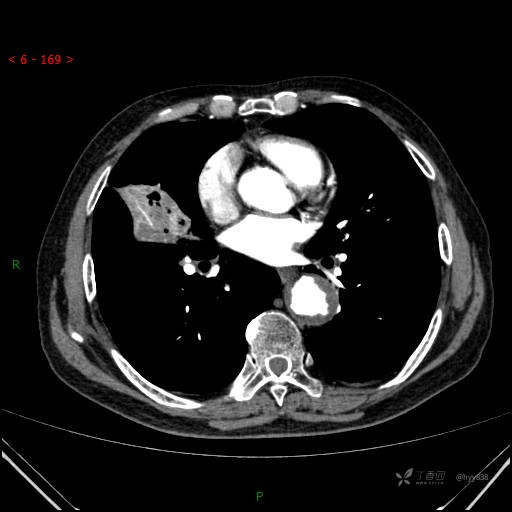

讨论:影像特征?病变性质?

增强动脉期

静脉期